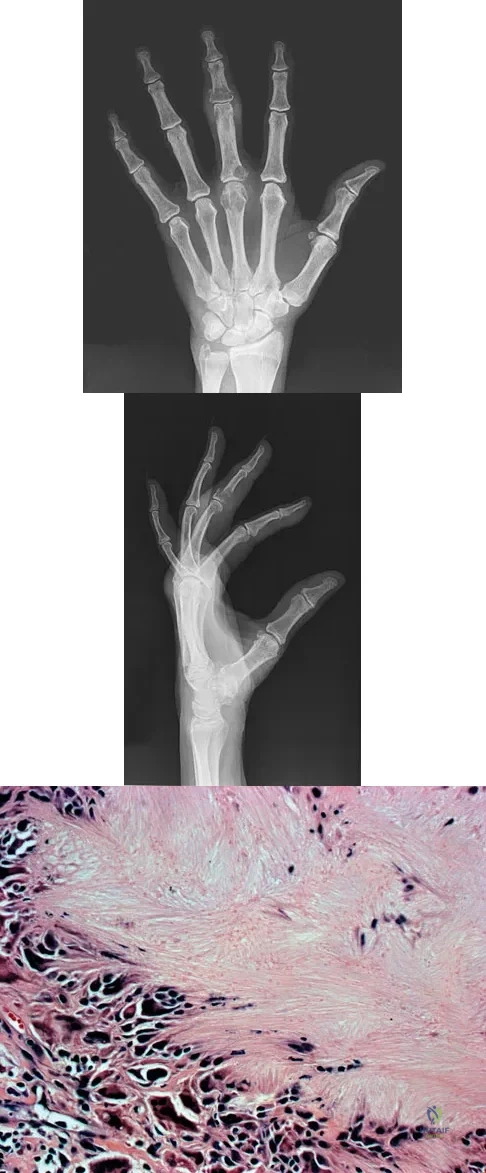

A 10-year-old boy has had wrist pain for the past 3 months. He denies any history of trauma. He reports mild tenderness associated with a palpable mass. A radiograph and biopsy specimens are shown in Figures 52a through 52c. What is the most likely diagnosis?

A 29-year-old woman reports shoulder pain after sustaining a minor fall 6 weeks ago. She has a history of celiac sprue. Radiographs of the forearm and shoulder are shown in Figures 53a and 53b. Which of the following serum abnormalities would be expected?